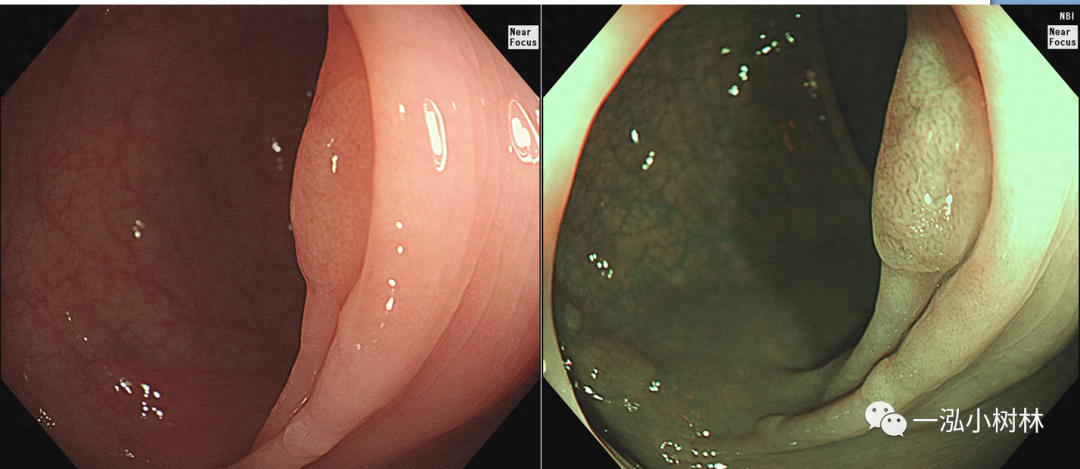

图4 结肠管状腺瘤(Pit Pattern IIIS+IIIL型)